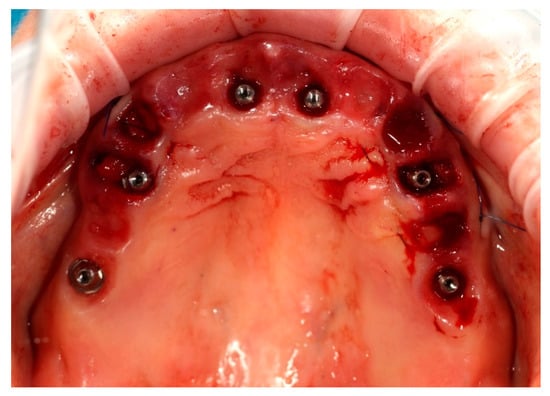

Simultaneously, the existing implant-supported crowns in positions 16 and 26, as well as the anterior implant-supported bridge, were unscrewed from the supporting implants. Multi-unit abutments were then selected and secured onto all six supporting implants, including the newly placed implants at sites 14 and 24 (Figure 4).

Figure 4. Multi-unit abutments secured onto all six supporting implants, including the newly placed implants at positions 14 and 24, following removal of the existing restorations.